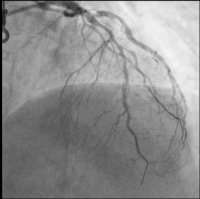

CX

Abbildung 3: CX: chronischer Verschluss eines Marginalastes